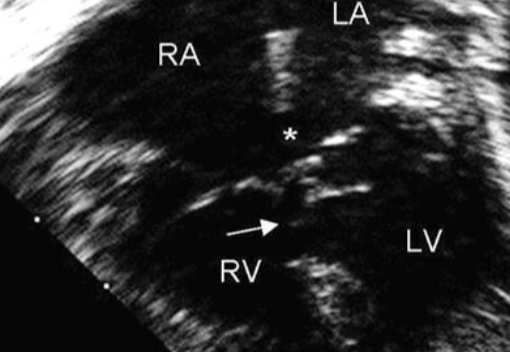

Investigation and likely diagnosis

- Echocardiography.

- Complete Atrioventricular Septal